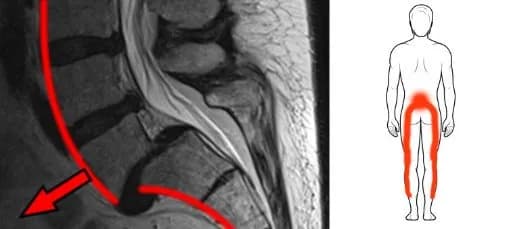

Ból kręgosłupa lędźwiowego: jaki lekarz pomoże w Twoim przypadku?

Szukasz lekarza na ból kręgosłupa lędźwiowego? Dowiedz się, który specjalista pomoże Ci w leczeniu i jakie kroki podjąć, aby poprawić swoje samopoczucie.

Problemy z kręgosłupem do jakiego lekarza? Sprawdź, kto pomoże

Masz problemy z kręgosłupem do jakiego lekarza się udać? Sprawdź, jakie objawy wskazują na potrzebę konsultacji i kto może Ci pomóc.